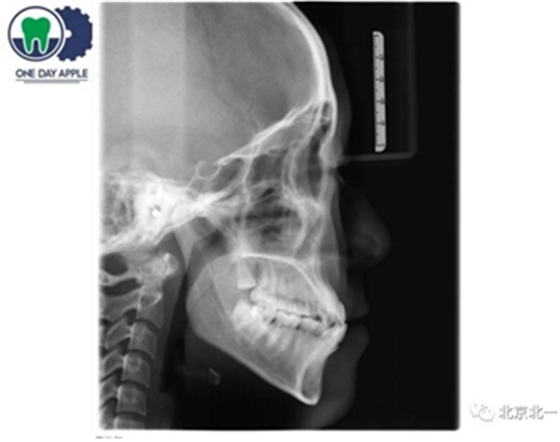

CBCT:骨量高度及宽度可, 48埋伏,低位阻生.37近中骨吸收

诊断:下颌牙列缺损, 48低位埋伏阻生 37 牙周炎